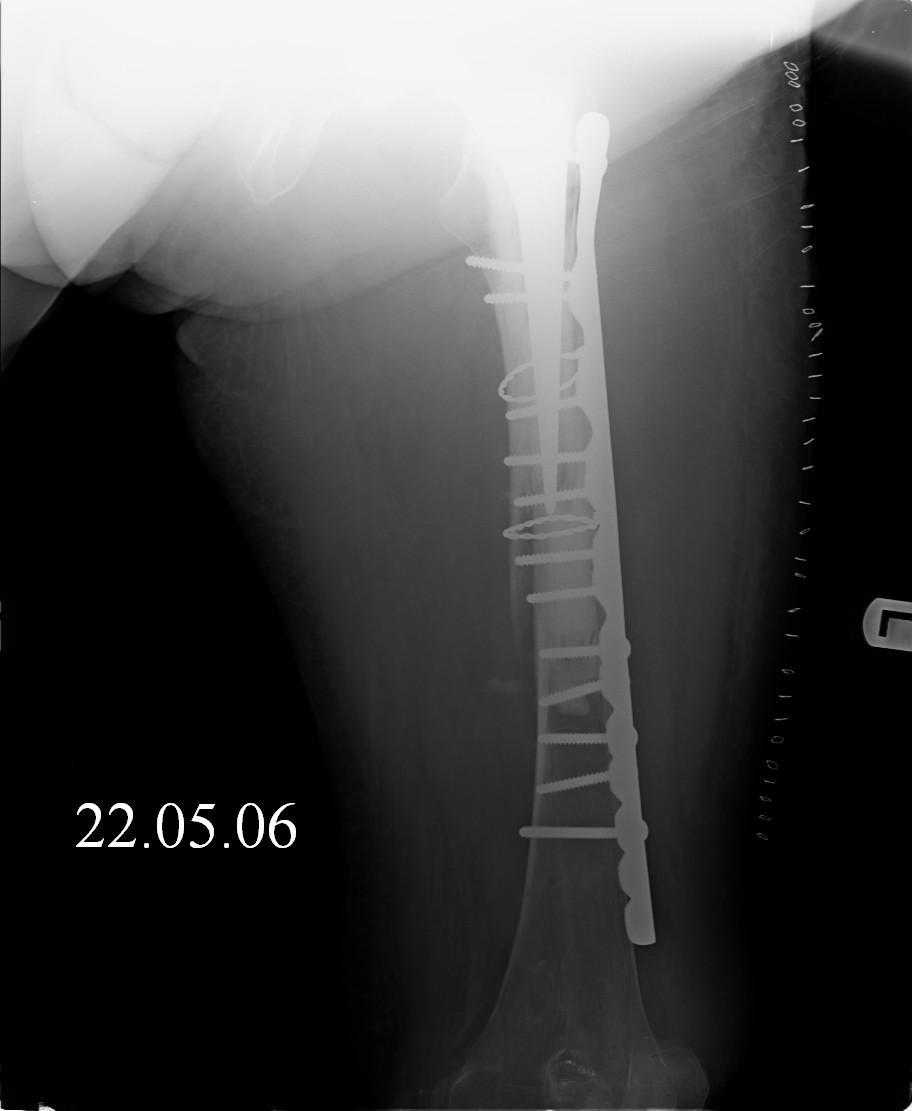

Re: Перипротезный перелом

Hello! This is just illustration in one of the choice of treatment